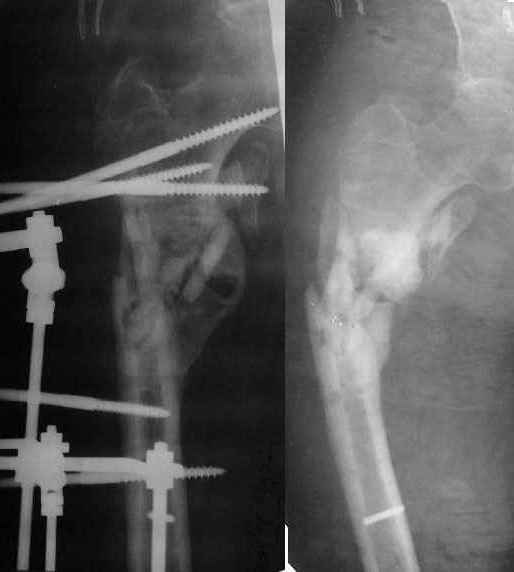

Здравствуйте, коллеги!!! К нам в отделение госпитализирован пациент 39 лет с клинико-рентгенологической картиной ложного сустава в/3 плечевой кости! Снимки прилагаются! Предистория такова: около года назад получил оскольчатый перелом в/3 плечевой кости. В одной из московских больниц выполнен остеосинтез пластиной, через несколько месяцев выполнен реостеосинтез, опять же пластной...., причины реостеосинтеза со слов пациента таковы - "доктору не понравилась как лежит пластина и он ее переложил..." - два месяца назад выполнено удаление фиксатора. Никаких выписок у больного нет. Около недели назад больной ударился областью плечевого сустава, появились боли, в связи с чем он обратился в травмопункт, откуда направлен к нам. Клинически у пациента имеется подвижность в области в\3 плеча, костная крепитация, умеренная болезненность в в/3 плеча при движениях, атрофия дельтовидной мышцы. На следующей недели планируем пациента опериравать. Коллеги, у нас возникло несколько вопросов, если не затруднит, то посоветуйте и подскажите... Мы планируем выполнить закрытый блокируемый остеосинтез, скажите пожалуйста, нужно ли в этом случае, на ваш взгляд, выполнять костную пластику или достаточно выполнить рассверливание костномозгового канала и заштифтовать толстым гвоздем, нужно ли пытаться удалить винты??? У нас в отделении идут дискуссии по этому поводу, придти к общему знаменателю не можем, поэтому и обращаемся к Вам!!! На основании ваших отзывов мы и примем окончательное решение!!! Спасибо!!! Очень ждем Ваших комментариев!!!

1. жизнеспособность головки плечевой кости, которая может быть установлена при КТ плечевого сустава. Если головка нежизнеспособная, то единственной альтернативой артродезу в данном случае является онкологический плечевой протез

2. характер ложного сустава и состояние костных отломков: четкая рентгенологическая картина гипотрофического (аваскулярного) ложного сустава с выраженным склерозом концов отломков и значительным дефектом костной ткани диктует необходимость введения в область ложного сустава остеоиндутивного материала (если бы не было значительного дефекта и склероза концов отломков в межотломковую область можно было бы ввести костную крошку, полученную при рассверливании костномозгового канала). В данном случае значительный дефект кости и плохое состояние концов требует: а)«освежения концов отломков», б) введения в область ложного сустава васкуляризированого костного трансплантатата, либо свободного костного аутоторансплантата, либо выполнение дистракционного остеосинтеза («костного транспорта»). При этом Вам естественно придется «открывать» область перелома, а значит Вы легко удалите винты.

3. состояние костной ткани поврежденного сегмента: в данном случае костная ткань остеопорозна, с многочисленными «дырами» от винтов, ранее фиксировавших пластины. Поэтому фиксировать пластиной третий раза нецелесообразно. Остаются 2 метода: блокированный штифт для проксимального плеча (Т2 страйкер или аналоги), либо аппарат внешней фиксации (чем лучше владеете).

Провести штифт в дистальный отломок закрыто вряд ли удастся: «сосулькообразный» конец отломка, запаянный костномозговой канал, дополнительное препятствие в виде 2 винтов.